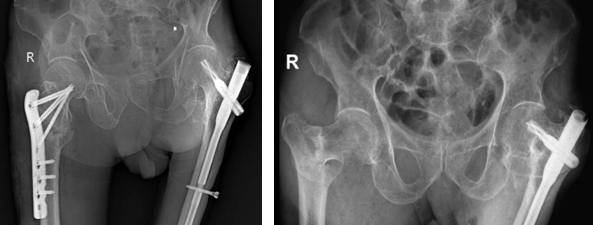

• Phương pháp kết hợp xương bằng đóng đinh nội tuỷ: Phương pháp này được chỉ định cho những trường hợp gãy xương phức tạp, gãy không vững và có thêm mảnh rời. Cụ thể, một số loại đinh nội tủy được sử dụng phổ biến gồm: Gamma, PFNA​​​​​​​

Đinh nội tuỷ PFNA

Nẹp khoá đầu trên xương đùi